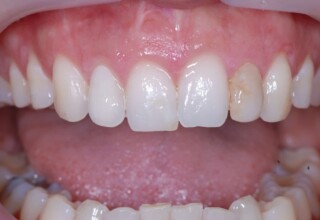

Composite Resin Veneers

Resin veneers are an inexpensive mode of esthetic improvement of anterior teeth, premolars also. Their potential is admirable and their limit is the operator’s clinical dexterity and imagination. In this case there were multiple problems with the upper four incisors: staining, poor inclinations, diastemas, multishading, poor interrelationship and poor tooth-gingiva ratios. They were restored with four direct composite resin veneers (one on a porcelain implant crown!) which were manufactured intraorally!!!